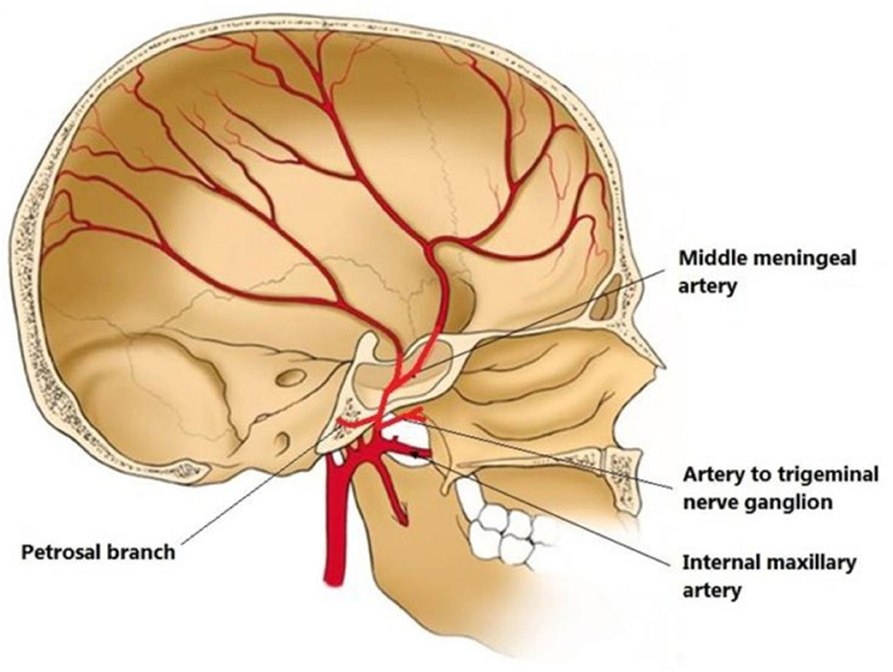

Анатомия: Задняя соединительная артерия мозга